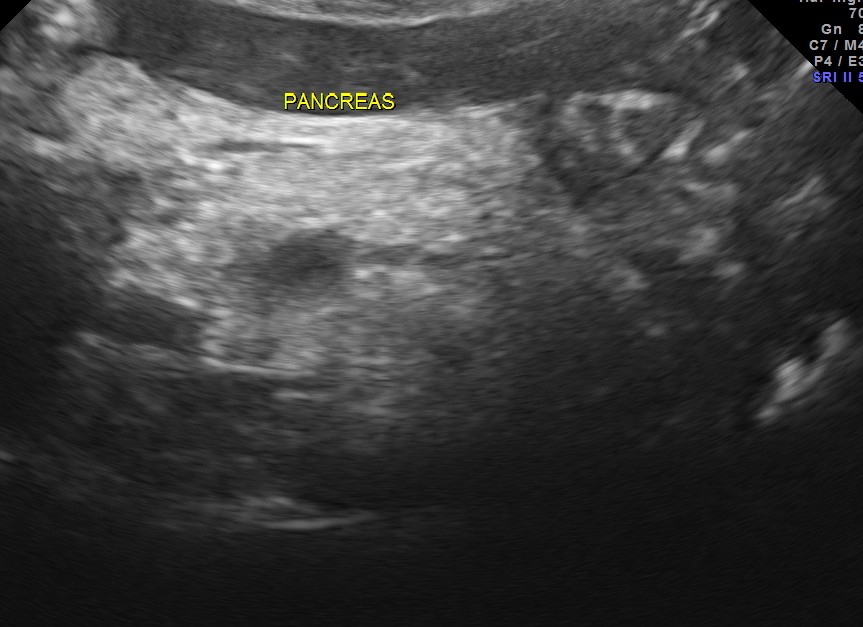

pancreas, spleen and both kidneys were normal.